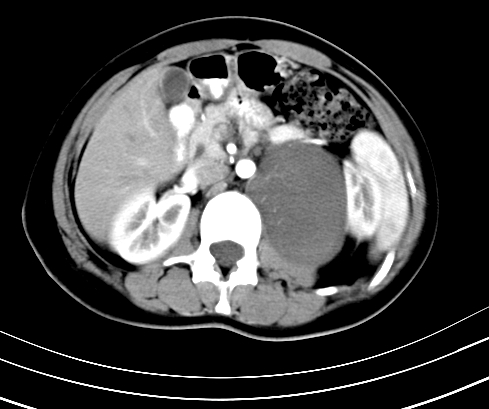

标题: CT23915:女 20岁 全身长疙瘩三年 今日多体位查 看看吧 [打印本页]

标题: CT23915:女 20岁 全身长疙瘩三年 今日多体位查 看看吧

腹部平扫

动脉期

神经纤维瘤病

支持神经纤维瘤。

支持 神经纤维瘤病。